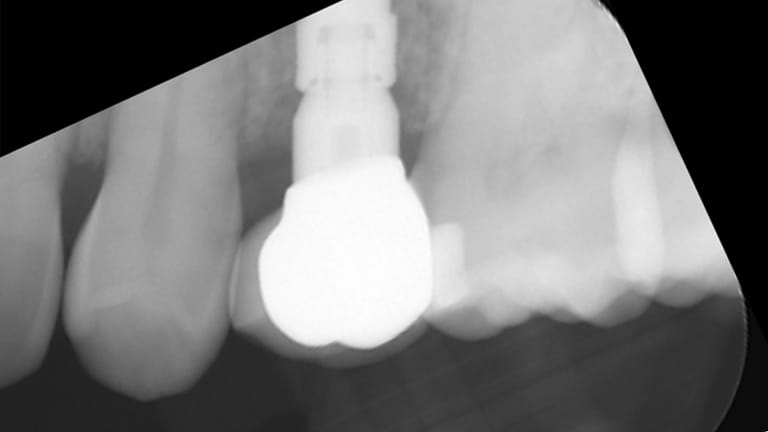

Single Tooth Replacement

Bad Tooth

Implant (With no crown)

Implant with crown